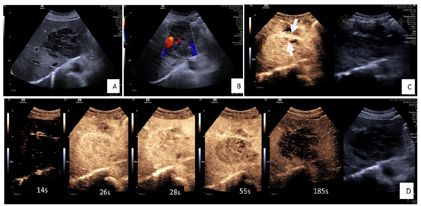

影像学检查:(1)CT平扫及增强(图1):肝左叶见类圆形略低密度影,最大截面约8.8 cm×7.1 cm,增强扫描不均匀延迟强化,并可见肝动脉、门静脉分支走形入病灶内,静脉期病灶边缘见两处低强化影向左外叶延伸(2处),邻近肝实质见斑片状强化影,右侧心膈角区及肠系膜区多发淋巴结影,大者大小约1.1 cm×0.8 cm,增强扫描轻度强化。(2)MRI平扫及增强(图1):肝左叶见团块状长T1、长T2信号影,DWI扫描示病灶主体呈高信号,边缘见条形高信号影向左外叶延伸(2处),同反相位无信号衰减,增强扫描病灶周边较明显强化,静脉期及延迟期强化程度减低,内部可见线样延迟强化影,另肝左叶动脉期见片状强化。(3)常规腹部超声及超声造影(图2):肝内低回声实性占位,边界清,形态欠规则,内及血流信号,超声造影动脉早期快速偏高增强,可见动脉自然穿过,无狭窄、扭曲,28 s开始廓清,延迟期持续低增强,呈"快进快出"恶性肿瘤模式。(4)PET-CT(图3):肝左外叶为主可见大小约8.8 cm×7.1 cm的低密度肿块显示,其内密度不均,代谢增高,伴左侧肱骨上段、胸6椎体附件、左侧第6肋可见多发溶骨性及成骨性骨质破坏灶,代谢增高,右侧心膈角区、腹主动脉旁淋巴结显示,大者约1.5 cm×0.5 cm,代谢增高。

本病的主要影像学表现为肝内单发病变、多发结节或弥漫型浸润,常伴有多部位、多组淋巴结同时受侵及其他结外脏器受侵。PHL以孤立性肿块多见,而SHL以多发结节或弥漫浸润多见[2]。根据本例影像表现,肝内虽为孤立性肿块,但结合患者淋巴结肿大明显,考虑为SHL。结合文献,笔者认为,本病的影像表现有以下特征:(1)表现为门静脉周围肿块样及分支样浸润病灶,可能与肝脏淋巴组织主要分布于这一区域有关,仅有很少病例报道这一征象[3]。此征象也可在朗格汉斯细胞组织增生症、肝细胞癌、胆管细胞癌的淋巴管扩散出现,但门静脉周围淋巴瘤无血管侵犯或占位效应。(2)增强扫描呈渐进性轻至中度持续强化,提示肿瘤乏血供,可能与肿瘤细胞密集度高而间质、微血管成分稀疏有关,与文献报道相符[4]。本病例肿瘤内未强化区经病理证实为肿瘤的坏死区域,与既往文献报道一致[5,6],亦有学者认为是纤维组织所致的类似肝脏局灶性结节样增生(focal nodular hyperplasia,FNH)的瘢痕结构[7],则表现为延迟强化,病理基础为肝星状细胞所致的肝纤维化对慢性肝损伤产生的修复反应。另外本病例病灶动脉期周边环形强化,静脉期及延迟期强化程度减低,Maher[8]认为此现象与病灶侵犯邻近正常肝组织导致的脉管炎有关。(3)增强扫描见"血管漂浮征",即病灶周围血管表现为受压变窄、推移、变形,但多无破坏中断,可见连续血管影,其病理学基础可能与肿瘤起源于肝脏间质,沿着肝组织的解剖结构浸润性生长,而对肝内固有血管破坏轻微有关,因此被认为是肝淋巴瘤的特征性表现[2],对诊断具有重要意义。(4)MRI成像呈T1WI低信号,T2WI等或稍高信号,DWI示弥散受限,相对其他肿瘤更明显,这与淋巴瘤肿瘤细胞密集度高有关[4],动态增强表现同CT。